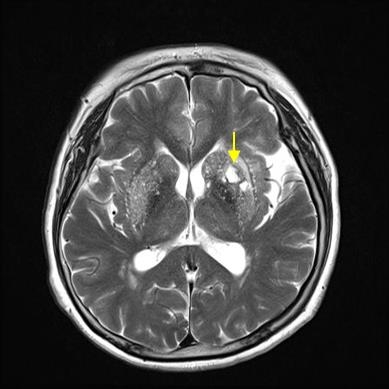

뇌의 혈관이 막혀 해당 영역의 뇌 일부가 죽는 상태입니다. 뇌혈전증과 뇌색전증이 있습니다. 심한 협착으로 인해 뇌로 가는 혈관이 완전히 막히거나 혈류가 현저히 감소하면 뇌 조직의 이 부분이 죽고 결국 녹습니다. 뇌연화증은 뇌세포가 죽어 부드러워지는 현상이고, 뇌성마비는 뇌경색으로 인해 뇌세포가 죽어가는 현상이다. 요약하자면 뇌혈관이 막혀 눈앞의 뇌조직이 괴사하는 질환이다.

뇌혈관이 막혀 뇌의 일부가 파괴되는 질환이다. 심장병이나 동맥 경화로 인해 발생할 수 있으며 이는 60세 이상의 사람들에게 더 흔합니다. 고혈압, 고지혈증, 당뇨병이 있는 사람들은 동반 증상을 경험할 수 있지만 날씨가 추울 때 노인들에게 더 흔합니다. 뇌의 특정 부위에 흔히 발생하며 한쪽 팔과 한쪽 다리의 마비가 뇌경색의 대표적인 증상이다.